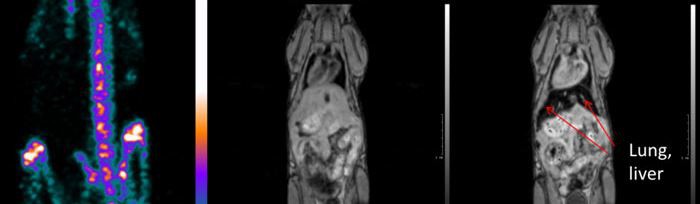

The new HCI study used mouse models to investigate a drug response of combining the two drugs simultaneously and applied advanced imaging techniques (nanoScan PET/MRI, supplied by Mediso USA, Boston and nanoScan SPECT/CT, Mediso, Hungary installed in HCI at the Center for Quantitative Cancer Imaging) to show the strong drug response.

Preclinical imaging. Mice were anesthestized and injected by approximately 0.5 mCi of [18 F]-fluorodeoxyglucose (FDG). CT imaging was performed using a NanoScan SPECT/CT scanner followed by PET and MRI imaging using a NanoScan PET/MRI scanner (Mediso Medical Imaging, Budapest). The animal remained anesthetized and immoblized in a common MultiCell animal chamber to provide intrinsic spatial co-registration of CT, MRI, and PET images. T1-weighted Gradient Echo (GRE) images and T2-weighted 2D Fast Spin Echo (FSE) images were acquired prior to initiating a 20-minute PET emission scan at 60 minutes post-injection of FDG. (Figures from this paper are publicly accessible at: https://www.nature.com/articles/s41591-019-0367-9)